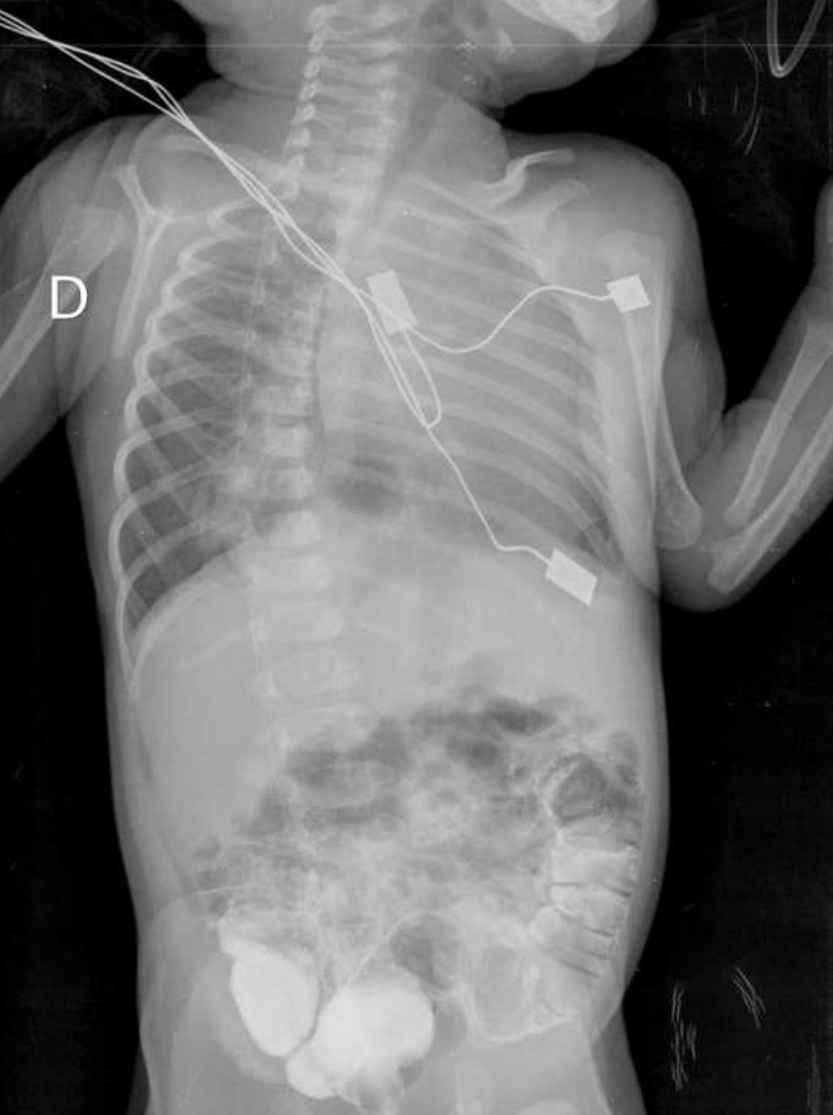

Figure 1: Thorax-abdomen X-ray showing absence of gastric bubble.

Figure 3: Thorax-abdomen X-ray after upper gastrointestinal contrast study showing a gastric bubble inside the thorax.